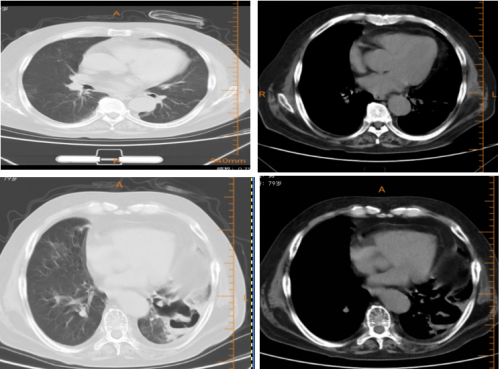

10月14日胸部CT检查:

10月15日